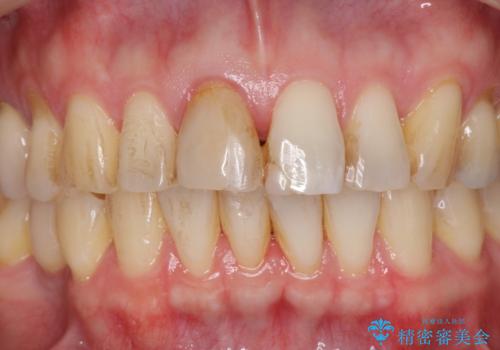

前歯の変色を改善!セラミック治療

- 前歯の変色が気になり審美障害の改善を求めて来院されました。

根管治療に伴う歯の色調変化はよく見られる所見です。

セラミッククラウン製作を行い審美性の改善を計画します。